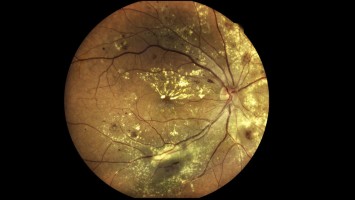

Bildnachweise